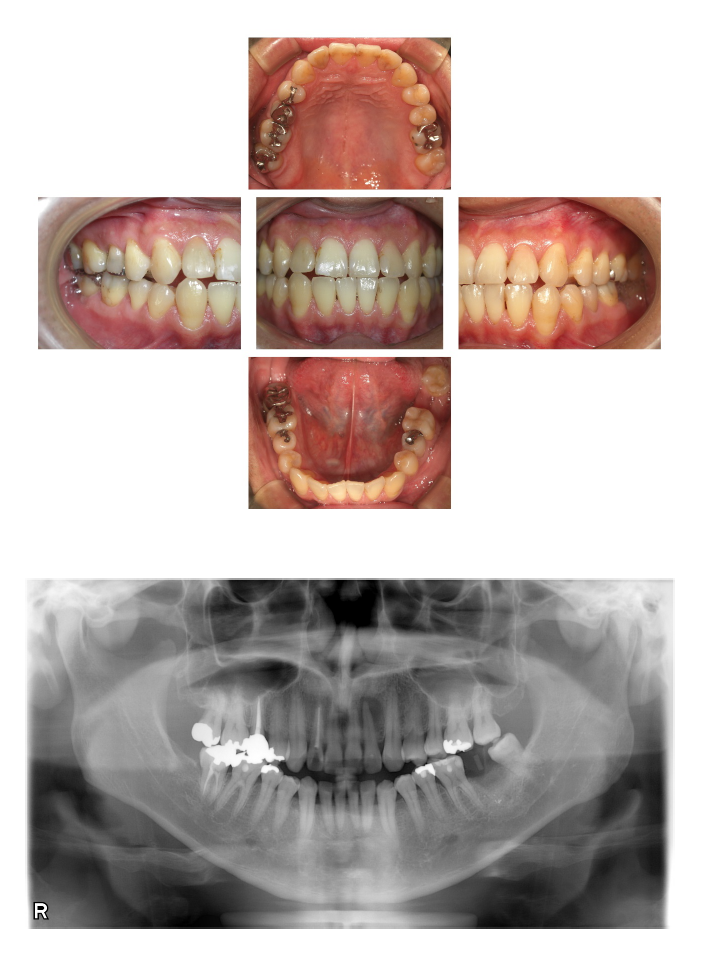

(術後)

治療内容:インプラント植立

治療期間:7か月

担当医からのコメント:初診時保存不可能で、かぶせを除去して内面が骨の下まで破折を起こしていることを確認。後日抜歯。抜歯直後にリテーナー(仮歯)を装着。5か月待機後インプラントを植立。インプラントを植立して8年経過をしますが、セルフケアも良く、歯肉や骨、噛み合わせに異常がなく経過良好です。メンテナンスも3ヶ月に1回定期的に当院で継続して行っています。